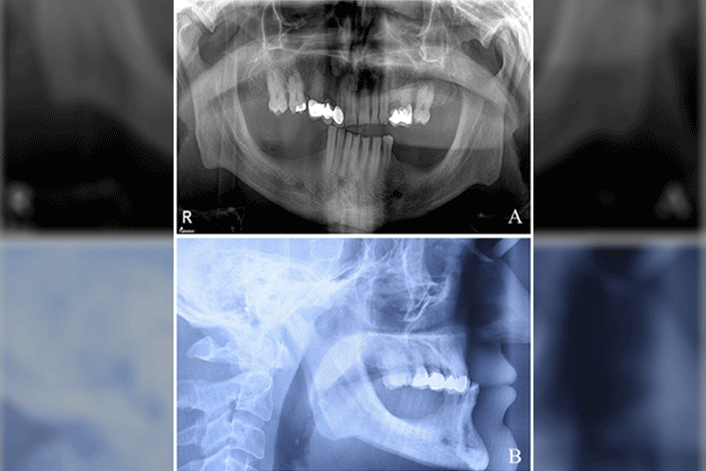

Now online in the Journal of Prosthodontics, Drs. Mehmet Berk Kaffaf, Pınar Şeşen, and Olcay Şakar present a clinical report on the treatment of a patient with acromegaly and a decreased occlusal vertical dimension. Acromegaly is a rare acquired disorder caused by excessive growth hormone production and prosthetic treatment of these patients is challenging.

In this case report, a partially edentulous patient with acromegaly and a decreased OVD was rehabilitated with a maxillary metal-ceramic partial fixed prosthesis and mandibular precision attachment RPD. The OVD was reestablished by increasing it approximately 10 mm. Four years after treatment, the patient was functioning well, and neither occlusal disharmony nor temporomandibular disorder was observed.